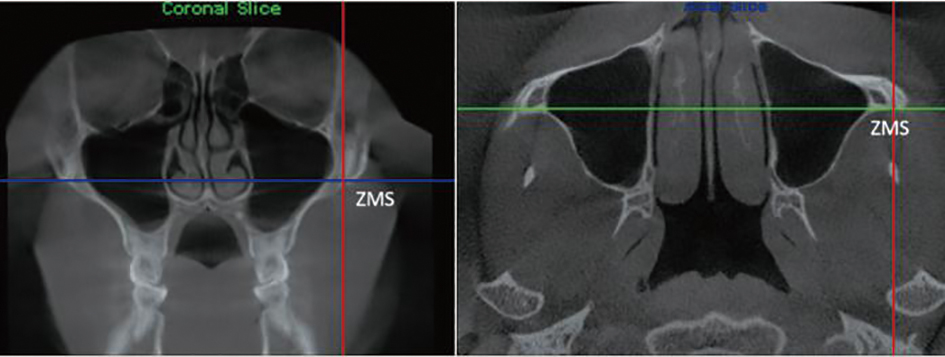

Objective To analyze the clinical outcome of microimplant screw-assisted maxillary rapid arch expansion in patients with Class Ⅲ malocclusion. Methods A total of 58 patients with Class Ⅲ malocclusion treated at Handan Stomatological Hospital from January 2022 to April 2023 were selected as the control group, and surgically assisted rapid maxillary arch expansion treatment was used. A total of 58 patients with Class Ⅲ malocclusion treated at Handan Stomatological Hospital from June 2023 to May 2024 were selected as the observation group, and micro-implant assisted rapid maxillary arch expansion treatment was performed. After 3 months of treatment, cone beam CT was taken to compare the bone structure, soft tissue measurement results, occlusal function, arch expansion effect, and postoperative complications between the two groups of patients before and after treatment. Results The bony width and the tilt of the supported teeth of the maxillary teeth increased in both groups after treatment, compared with the preoperative period(P<0.05). The nasal width of the maxillary first molar in the observation group increased significantly, and the tilt of the supported teeth were all reduced significantly compared with the control group(P<0.05). After treatment, ANB and LI-MP of the observation group were higher than those of the control group; SNB and MP-SN were lower than those of the control group. Facial convexity angle and nasolabial angle were higher than those of the control group; chin-labial angle was lower than those of the control group, and occlusal function was higher than those of the control group(P<0.05). The postoperative complication rate of 1.72% in the observation group was lower than that of 13.79% in the control group, with a significant difference(P<0.05). Conclusion Micro-implant-assisted rapid maxillary arch expansion can achieve obvious bony expansion effect, promote the improvement of the patient’s bony structure, improve their facial morphology, and enhance their occlusal function, which can be promoted and applied.